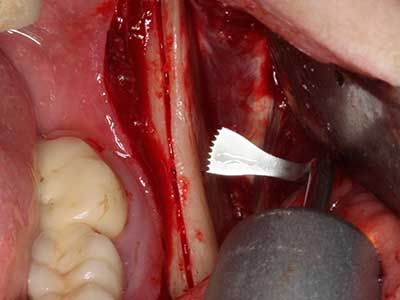

Bei der Knochenblockentnahme zeigen sich weitere Vorteile für die Piezochirurgie: Neben der bereits beschriebenen hohen Präzision bei der Osteotomie stellt sich gerade die Verwendung der dünnen Sägespitzen als besonders materialschonend heraus. Bei der Verwendung insbesondere von Lindemannfräsen sind mit deutlich höheren Entnahmeverlusten durch die dickere Instrumentenspitze zu rechnen (Lakshmiganthan, Gokulanathan et al. 2012). Die insbesondere bei retromolar entnommenen Blocktransplantaten notwendige basale Abtrennung wird durch speziell hierfür vorgesehene rechtwinklige Sägen erleichtert, so dass die Piezochirurgie als präzises, übersichtliches und sicheres Verfahren zur retromolaren Knochenblockgewinnung angesehen wird (Happe 2007) (Abb. 1-12).

Sollen chirurgische Eingriffe mit unmittelbarer Knochenbeziehung an empfindlichen Strukturen wie Blutgefäßen oder Nerven erfolgen, so bergen rotierende Instrumente ein erhebliches Potential an iatrogener Schädigung. Gerade bei Nervdarstellungen nach iatrogener Schädigung, oder aber im Zuge einer Nervlateralisation für resektive und rekonstruktive Eingriffe oder Implantatinsertionen können piezoelektronische Geräte hilfreich sein Knochendeckel zu präparieren und nervnahe Hartgewebsanteile zu entfernen (Abb. 17-20). Ein leichter Kontakt des Nervstrangs zur Piezospitze bleibt dabei in der Regel folgenlos – allerdings kann eine unvorsichtige Vorgehensweise mit sägeartigen Bewegungen bzw. Ansätzen bei noch vorhandener knöcherner Unterlage durchaus temporäre oder aber auch permanente Nervschädigungen verursachen. Das Risiko einer solchen Schädigung wird jedoch als wesentliche geringer eingeschätzt als unter Anwendung von Säge- oder Fräsinstrumenten (Pereira, Gealh et al. 2014).